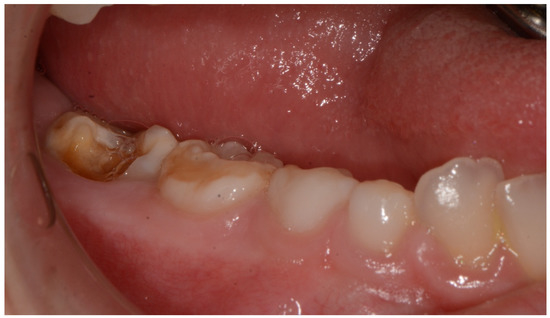

| Present study 2021 | 1 patient | M | high narrow palate, crowding, molar incisor hypomineralization (MIH), second class | 9 |